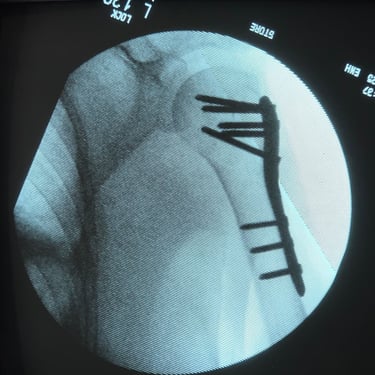

Paciente fémina de 70 años de edad, muy activa e independiente, presenta fractura de húmero proximal multifragmentada. Se opta por tratamiento quirúrgico en el cual se obtienen resueltados excelentes. Actualmente en fisioterapia y realizando actividades de la vida diaria sin limitaciones

FRACTURA DE HUMERO PROXIMAL